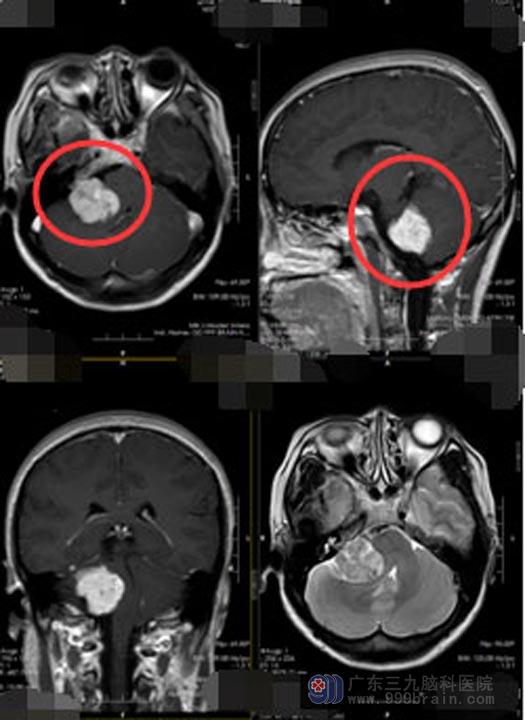

入住神经外五科进一步检查后发现,赵女士的颅内是长了两个肿瘤,一个位于右侧桥小脑角区,大小约3.1cm×2.6cm×3.3cm,增强扫描明显强化,考虑神经鞘瘤;另一个位于左侧额部镰旁,大小约为0.8cm×l.4cm,考虑脑膜瘤。

▲手术前